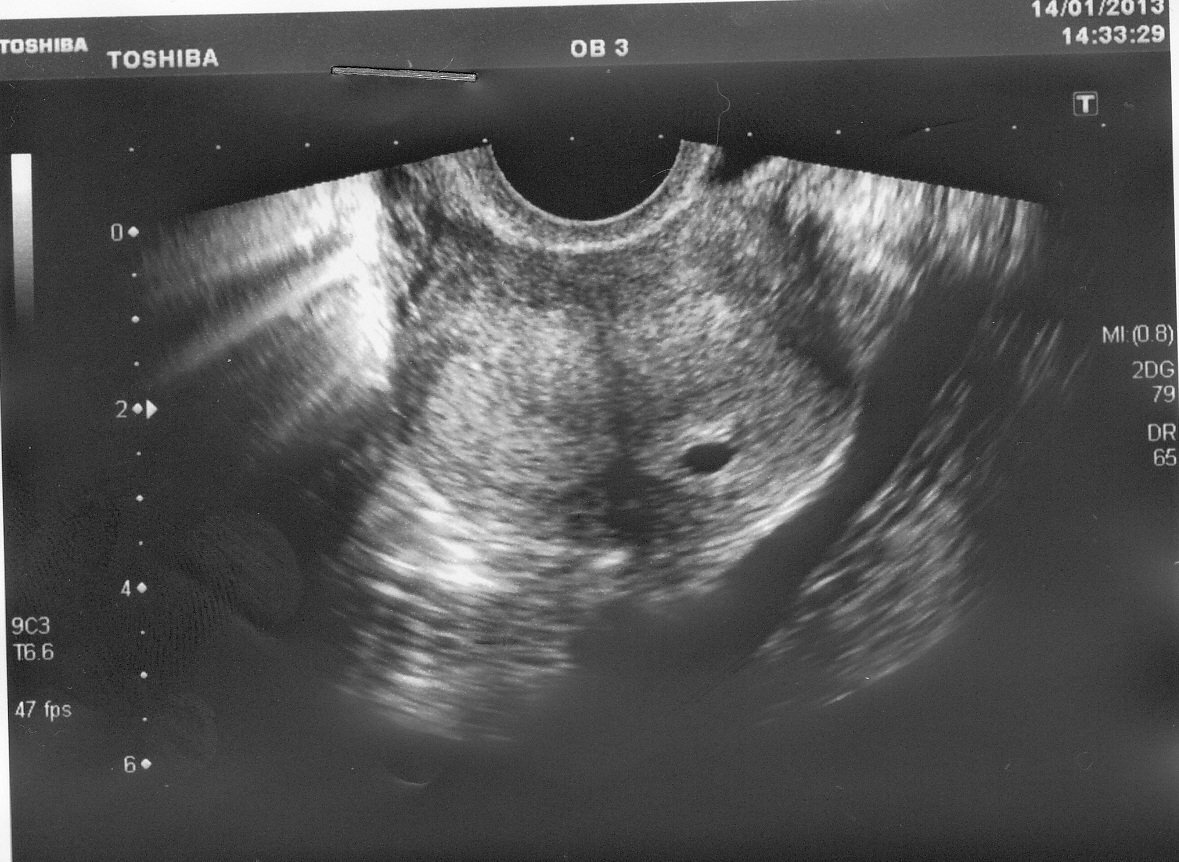

Два с половиной месяца назад у меня случился выкидыш. На тот момент у меня было 2 месяца беременности. Беременность была желанной, хоть и незапланированной.

Забеременела я в 40 лет перед самым Новым годом. Это была моя третья беременность. Мы с мужем были счастливы от одной только мысли, что у нас будет еще один малыш.